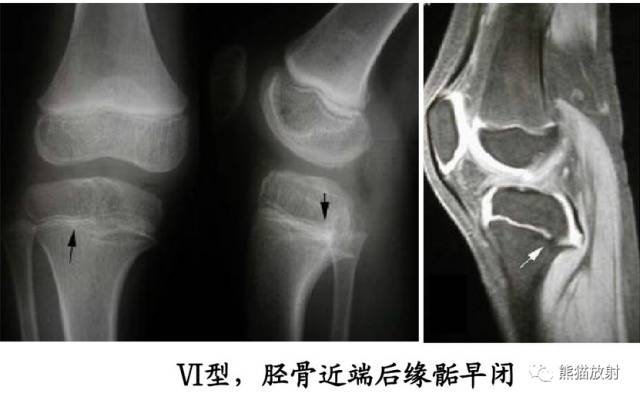

V型:骺板挤压性损伤(少见,多在晚期发生生长障碍时才能作出诊断)

第五型(V型) 骺板挤压性损伤,少见,占骨骺损伤的1%。由于严重暴力损伤造成,相当于骺板软骨的压缩骨折,有学者指出此型损伤只发生在一个方向活动的关节,如膝关节和踝关节。由于软骨细胞严重损伤破坏或来自骨骺营养血管广泛损伤,导致骺板早闭和生长停止。逐渐出现骨骼变形和关节畸形 ,但早期X线表现常常为阴性结果,多在晚期发生生长障碍时才能作出诊断。